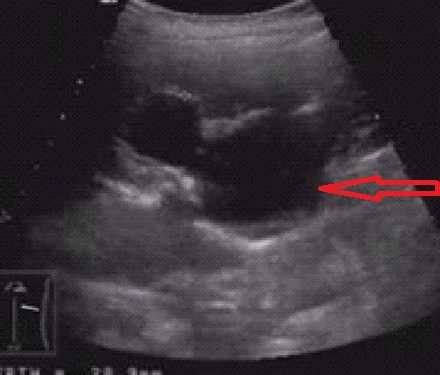

Ультразвуковое исследование

Ультразвуковое исследование. Диалатация чашечно-лоханочной системы.

При подозрении на данную патологию исследования проводят полипозиционно, оценивают состояние почки, лоханок, мочеточника, сосудов. Для корректного диагноза используют сравнение со здоровой почкой.